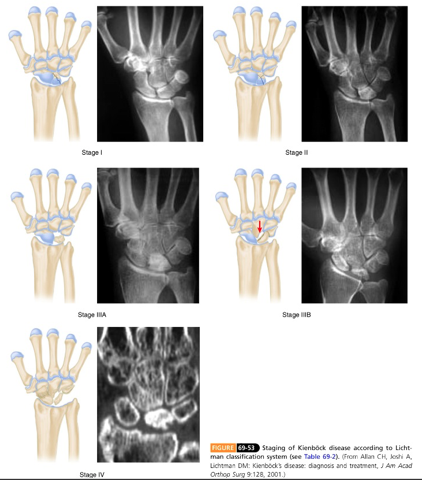

Classificação de Litchman

Baseada no Rx